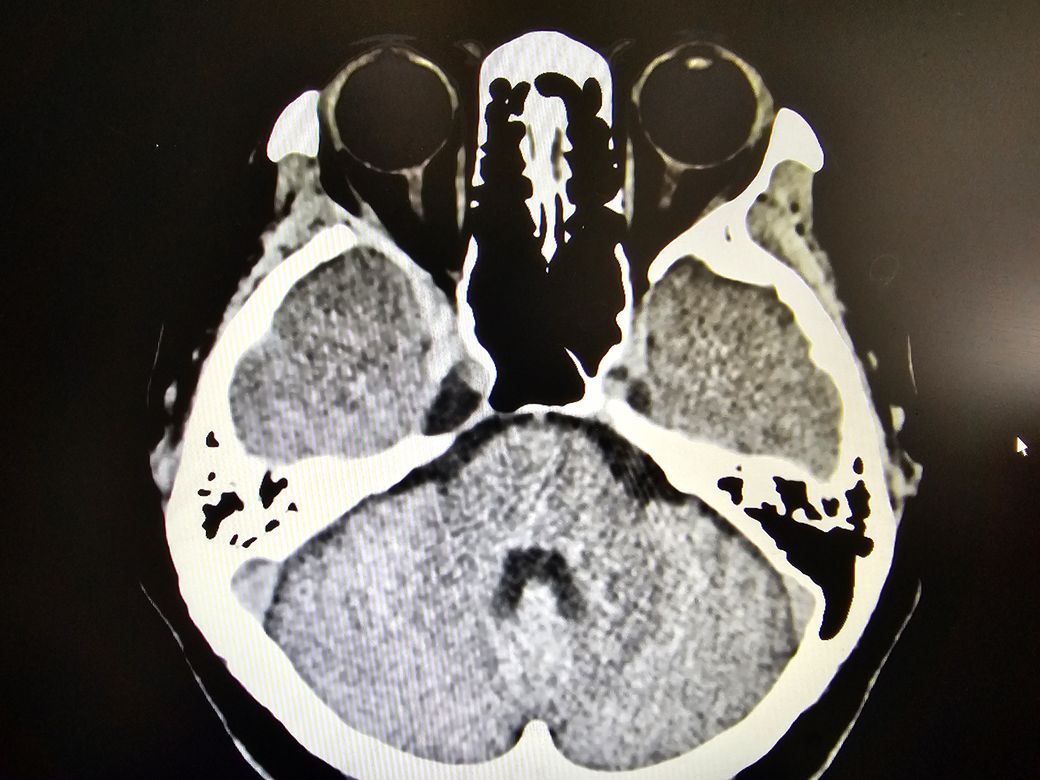

5년전에 오른쪽 뇌에 양성 뇌종양수술을 했고 얼마전 아침마다 일주일이상 같은 시간에 같은 증상의 쇠신이마두통이 심해서 준종합병원에서 ct를 찍었는데 종양이 재발됐고 8.6미리라고 하셨고 수술한 병원에서 다시 mri를 찍어보고 감마나이프 수술을 하라고 하셨는데 불안한 마음이 질문드립니다.

안녕하세요. 영상의학과 전문의 최원제 의사입니다.

올려주신 사진만으로는 뇌종양 여부를 판단하기가 어렵습니다.

CT를 찍은 준종합병원에서 판독이 나왔을 테니, 판독지를 확인해보시기 바랍니다.